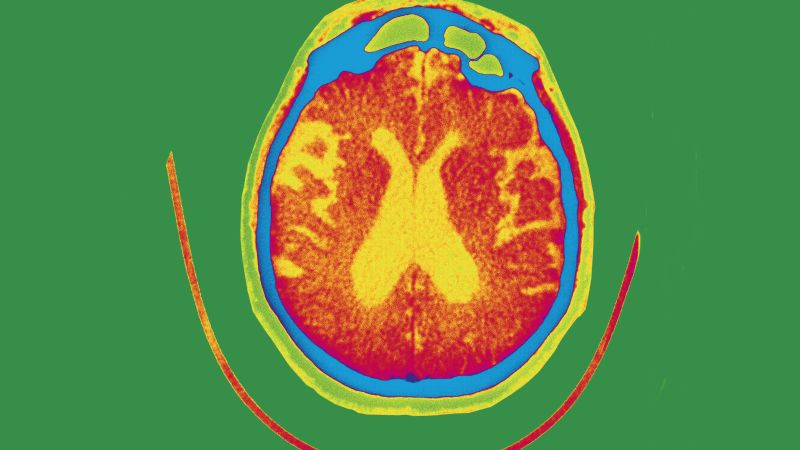

Gantenerumab is part of a class of injected drugs that are designed to remove sticky protein pieces called beta amyloid from the brain. Beta amyloid buildup is a hallmark of Alzheimer’s disease.